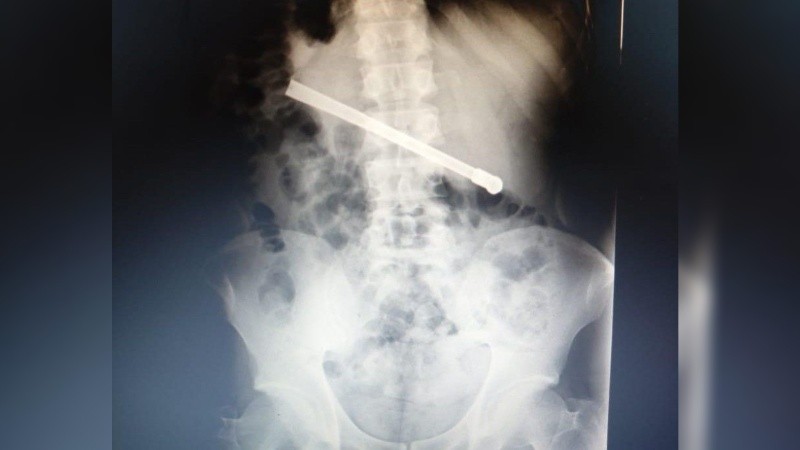

Al continuar con el malestar, le realizaron una placa radiográfica en la Unidad Penitenciaria ubicada en 27 de febrero al 7800, y pudieron determinar que había ingerido una bombilla de mate que quedó alojada transversalmente en la cavidad torácica.